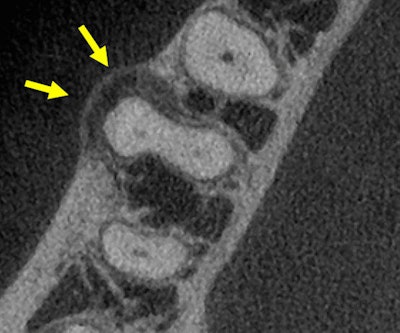

Figure 1: Cone-beam computed tomography image, sagittal view, tooth #30.Images courtesy of Dr. Juan F. Yepes.

Figure 2: CBCT, axial view, tooth #30.

"Small hypodense lesions (radiolucent) are observed at the mesial and distal apices of tooth #30. The lesions are well defined and well corticated. There is no evidence of expansion in the coronal and axial projections for the small lesion at the distal apex. However, there is evidence of expansion (buccal) of the hypodense lesion located at the apex of the mesial root. Hyperdense bone is present at the periphery of the lesion, indicating a chronic inflammatory process."